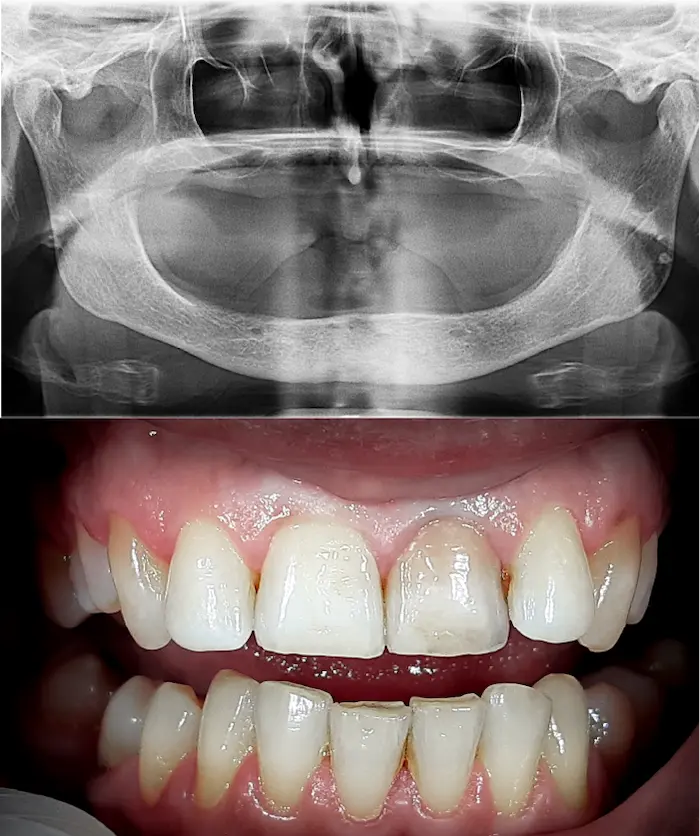

Molti pazienti arrivano con una storia simile:

Portano una dentiera mobile da molti anni

Non hanno abbastanza osso mascellare per gli impianti

Hanno perso i denti in giovane età e l'osso si è ritirato

Soffrono di atrofia muscolare importante

Sono soggetti a piorrea e mobilità dentale

Hanno già chiesto diversi pareri, senza successo

Queste condizioni rendono impossibili gli impianti fissi tradizionali o le riabilitazioni All-on.

E infatti molti professionisti li sconsigliano.

Una soluzione esiste: con gli impianti dentali zigomatici e gli impianti subperiostali (o impianti sottoperiostei) puoi ottenere denti fissi anche in assenza totale di osso mascellare.